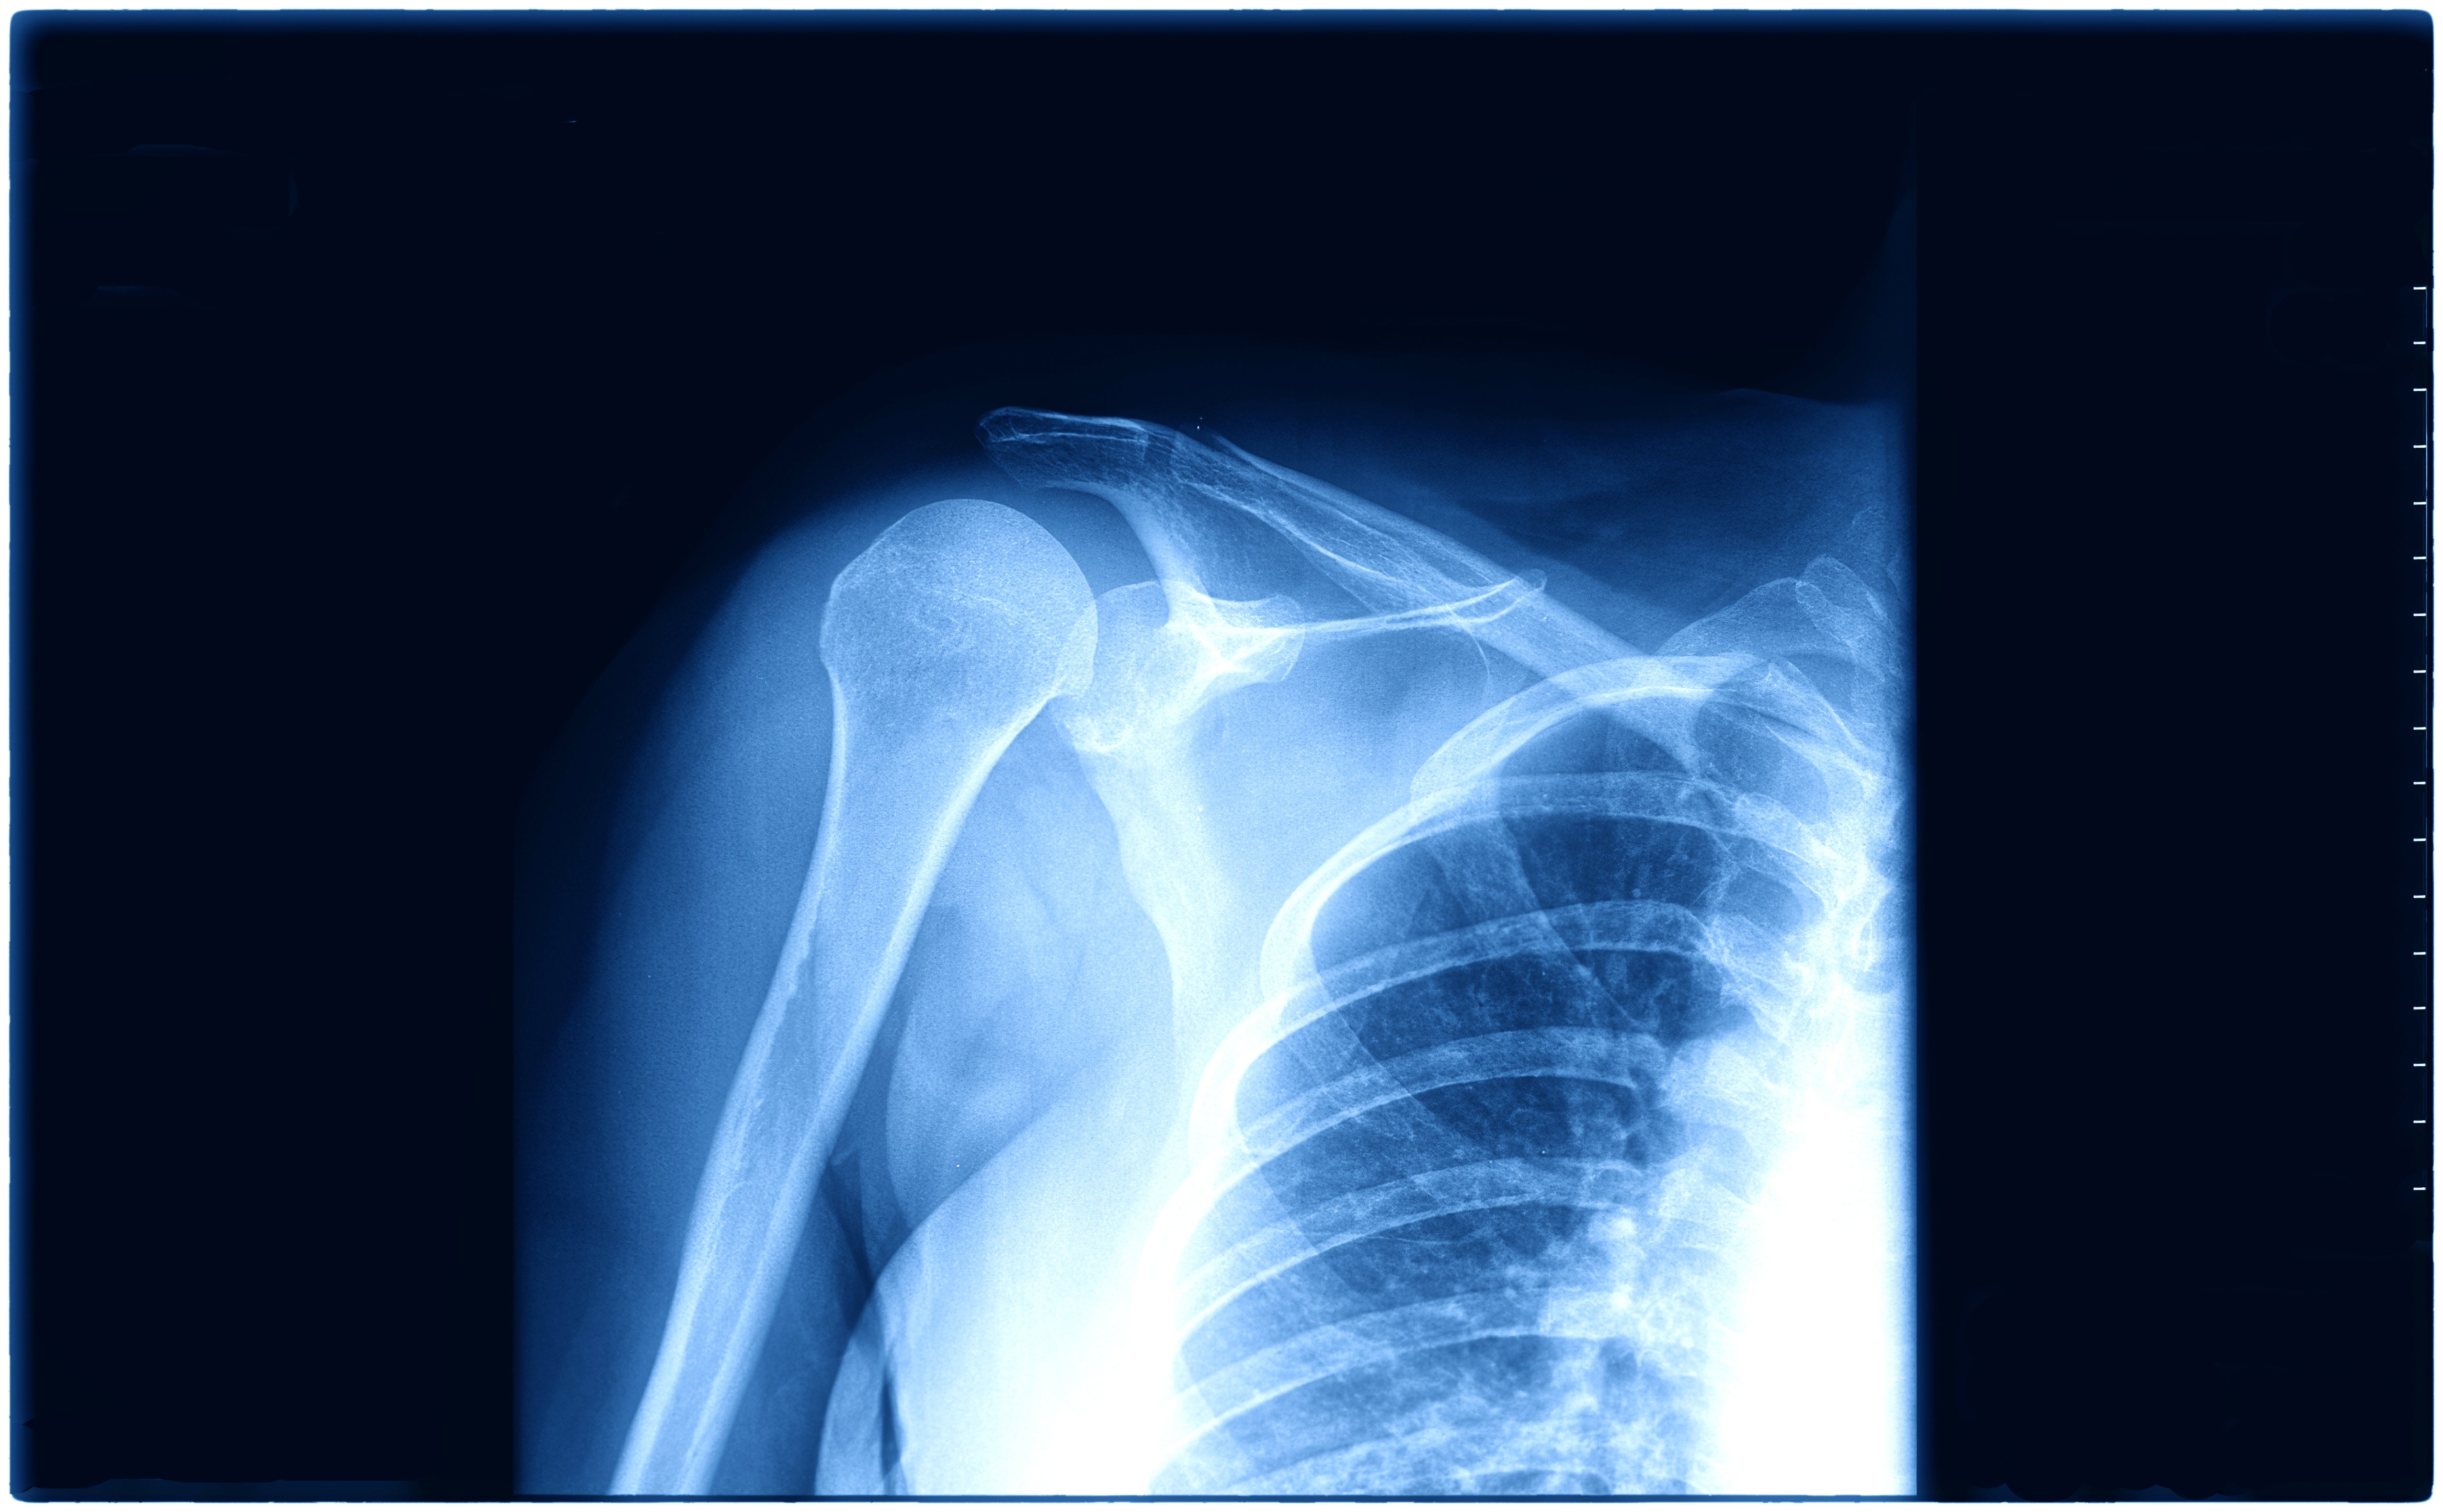

Inestabilidad de Hombro: ¿Ejercicios en cadena abierta o cerrada?

Kinesiofobia e inestabilidad anterior de hombro

Síndrome subacromial, el fin de una era.

Síndrome subacromial: evolución de una etiología controvertida y su tratamiento El síndrome subacromial (SS), también conocido como dolor de hombro relacionado con el manguito rotador, es una de l...